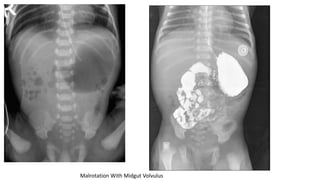

Malrotation With Midgut Volvulus

• Malrotation is caused by an abnormal rotation of bowel on itself, resulting in volvulus and bowel ischemia or

death.

• Malrotation occurs in 1 / 5000 live births and is usually diagnosed in the 1st month of life.

• The presenting symptoms : include bilious emesis and poor feeding, or lethargy and shock

• Abdominal radiographs may be normal, have signs of small bowel obstruction, or the classic

"double bubble" sign may be present.

• An upper gastrointestinal (GI) study with contrast is the gold standard for diagnosis, but an

abdominal ultrasound may also be helpful in an experienced technician's hands.

• Confirmation radiographic studies should never delay surgical consultation or transfer to an

appropriate pediatric facility

• Initial management includes stabilization of the ABCDE, fluid resuscitation, a nasogastric tube

placement, and pediatric surgical consultation